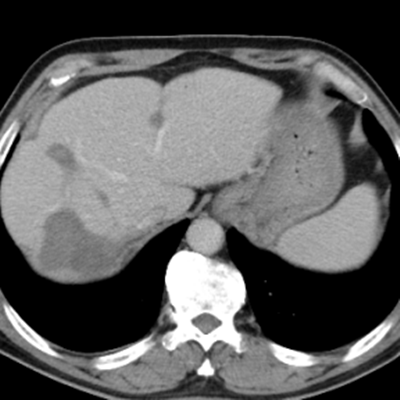

組織腸癌MDT診療團(tuán)隊(duì)進(jìn)行病情討論,診斷為腸癌伴肝、肺、腹腔、縱膈轉(zhuǎn)移,其中肝轉(zhuǎn)移瘤數(shù)目在50枚以上,最大的約10cm,并伴有腸梗阻,情況不容樂觀。

隨后,根據(jù)基因檢測結(jié)果制定了化療+靶向治療方案。經(jīng)過精準(zhǔn)治療,劉大爺?shù)牟≡畲笮⊙杆倏s小,病灶數(shù)量不斷減少,影像學(xué)評(píng)估已經(jīng)看不見之前那些小的病灶了。

治療后:未見明顯活性轉(zhuǎn)移腫瘤